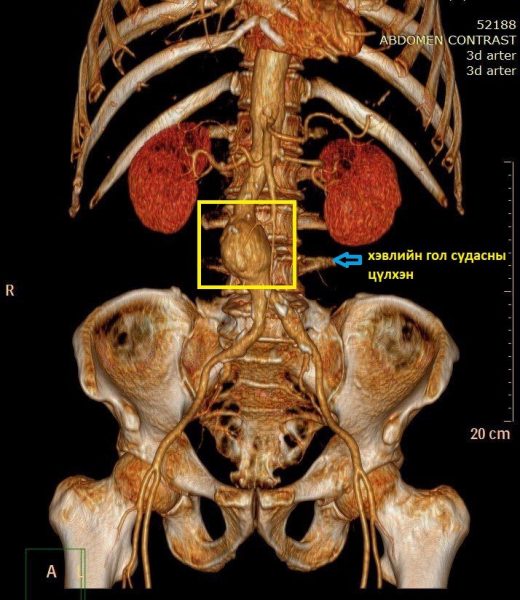

Хоёр ташааны тараагуур судас хамарсан хэвлийн гол судасны цүлхэн оноштойгоор тус эмнэлгийн Зүрх судасны мэс заслын эмч нарын хяналтад байсан 63 настай эмчлүүлэгчид төлөвлөгөөт журмаар, ерөнхий унтуулгын дор хоёр гуяны тараагуур судсаар дамжуулан хэвлийн гол судасны хүнд хэлбэрийн цүлхэнд нэхмэл полиэстр материал бүхий өмсгөлтэй стент графтийг байрлуулж, цүлхэн хагарч цус алдах хүндрэл болон улмаар амь нас эрсдэх аюулаас зайлсхийж чадлаа.

Судсан дотуурх эмчилгээний энэхүү арга нь гол судасны цүлхэн задрах, хуурах, хүндэрч нас барахаас сэргийлэхэд ихээхэн үр дүнтэй шинэ дэвшилтэт технологи бөгөөд сүүлийн жилүүдэд олон улсад эрчимтэй нэвтэрч байгаа бөгөөд тус эмнэлэг энэхүү эмчилгээний технологийг Монгол улсад, өөрийн эмнэлгийн зүрх судасны лавлагаа тусламж үйлчилгээнд нэвтрүүлж, нутагшуулахыг зорьж байгаа юм.